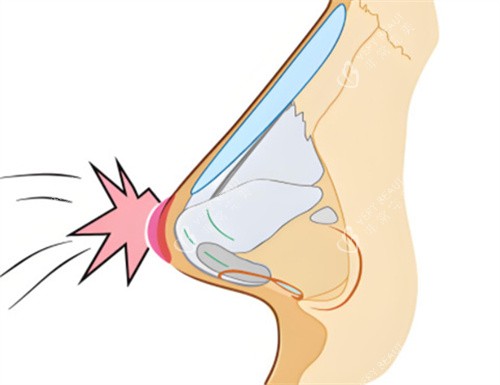

3. 小创口切口:1cm内的“更准一些植入”

通过鼻腔内切口植入雕刻后的假体,避开鼻部主要血管和神经,术中出血量减少,术后淤青消退时间缩短。

假体与鼻骨贴合度误差小,避免传统技术因张力过大导致的皮肤穿透风险。